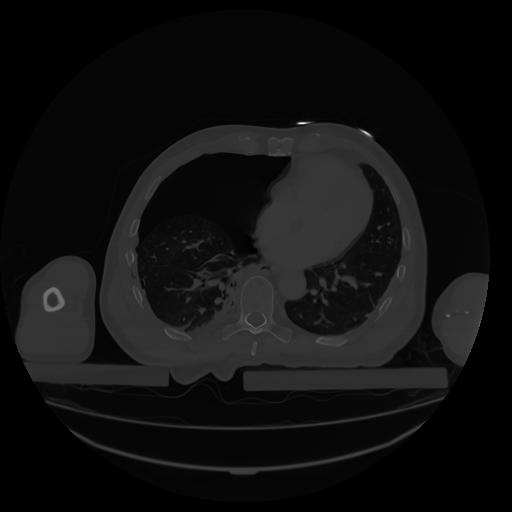

34 CUERPO,CE,Vol,1.0,CUERPO,,